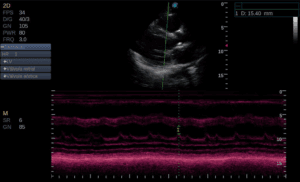

A vascular imaging modality is necessary to diagnose an AVM and assist in treatment decision making. Formal vascular ultrasound is usually the first imaging modality used due to its ability to be performed at the bedside, low cost, and no radiation or contrast exposure. Ultrasound is limited in its ability to determine depth of invasion into surrounding structures. MRI or CT-angiogram provides better spatial context along with hemodynamic information. The gold standard in diagnosis is a catheter based digital-subtraction angiogram [9]. Angiography distinctly shows the vasculature and allows for therapeutic guidance based off the resulting images.